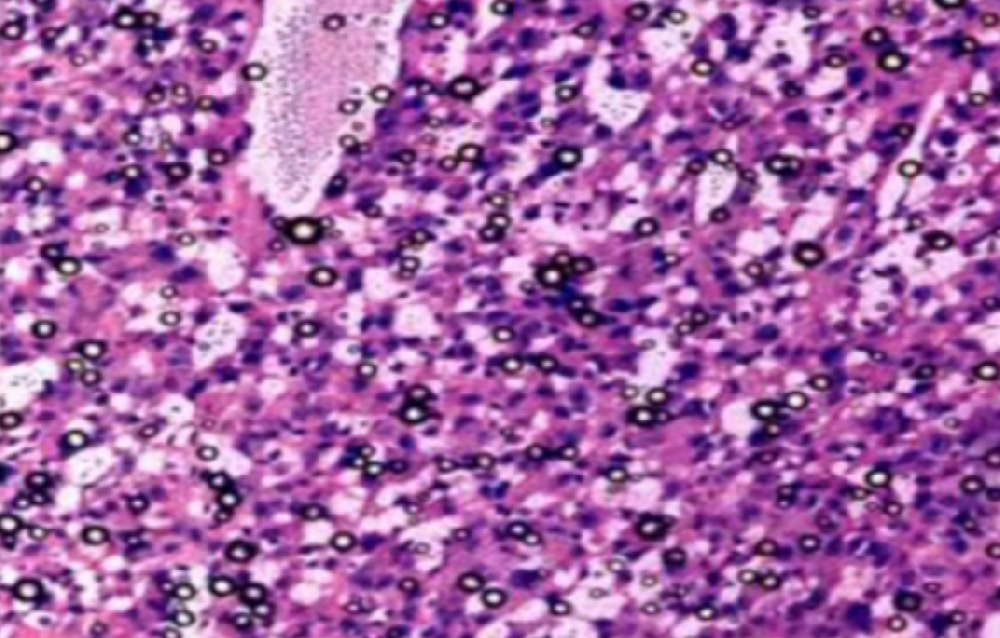

海东组织病理学实验

Current Biology | 巨噬细胞通过细胞因子扩增加速肿瘤生长

通过对巨噬免疫细胞在肿瘤中遭遇濒死癌细胞过程的研究,名古屋大学科学家发现了一种加速肿瘤生长的机制。当肿瘤内部癌细胞开始死亡时,其表面会暴露出濒死信号。巨噬细胞随···